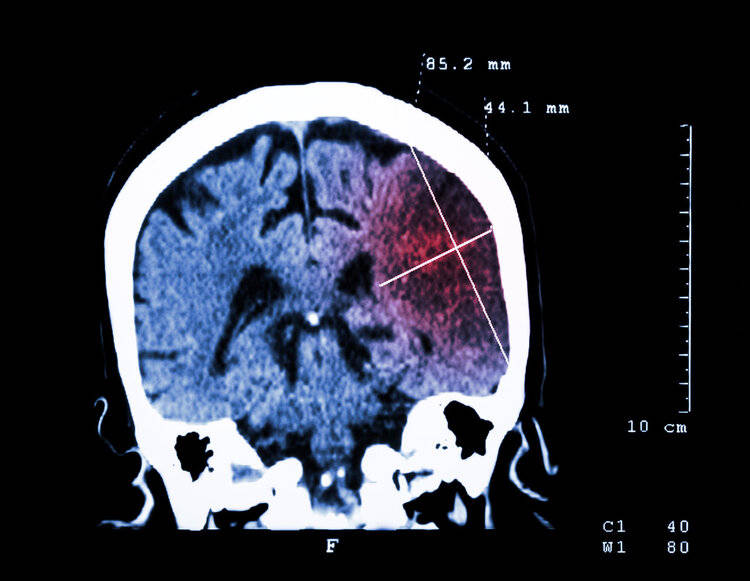

午睡醒来后,王阿姨发现自己连水杯都端不稳,走路时右腿直打晃。见休息也不能缓解,王阿姨心生不妙,赶忙让老伴带着她医院。送医后,CT显示她已突发大面积脑梗。